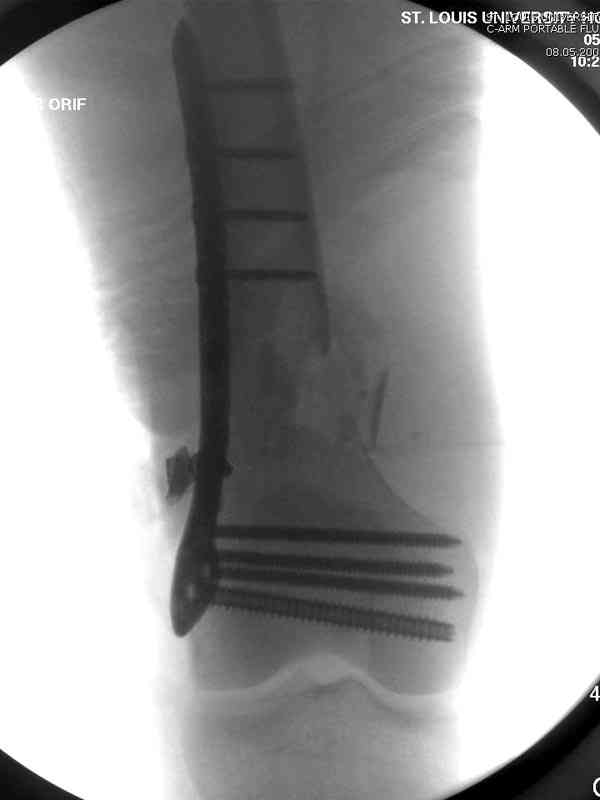

В данном случае мы не ставили осуществление гемостаза приоритетным, после 30 минут больной оставлен вызванному сосудистому хирургу со стабильной фиксацией бедра. Несмотря на выбранный передне-медиальный доступ, хирург произвел восстановление сосудистого повреждения.

Латерально пластину защитили ушиванием

илио-тибиального тракта, а медиальная сторона была ушита мышцей, и все раны закрыли ваккумированием (VAC)

На третий день после Irrigation & Debridment закрыли все раны за исключением компартментальной раны из-за отека, медиально в дефект кости установили Putty Grafton Bone Substitute. На компартментальную рану вакуум и мероприятия по сближению краев раны резиновой стяжкой.

На 9й день с момента травмы ушили рану без натяжения. Больной получает реабилитацию, движения коленного сустава с помощи CPM-continuous passive motion machine. Сегодня выписан.